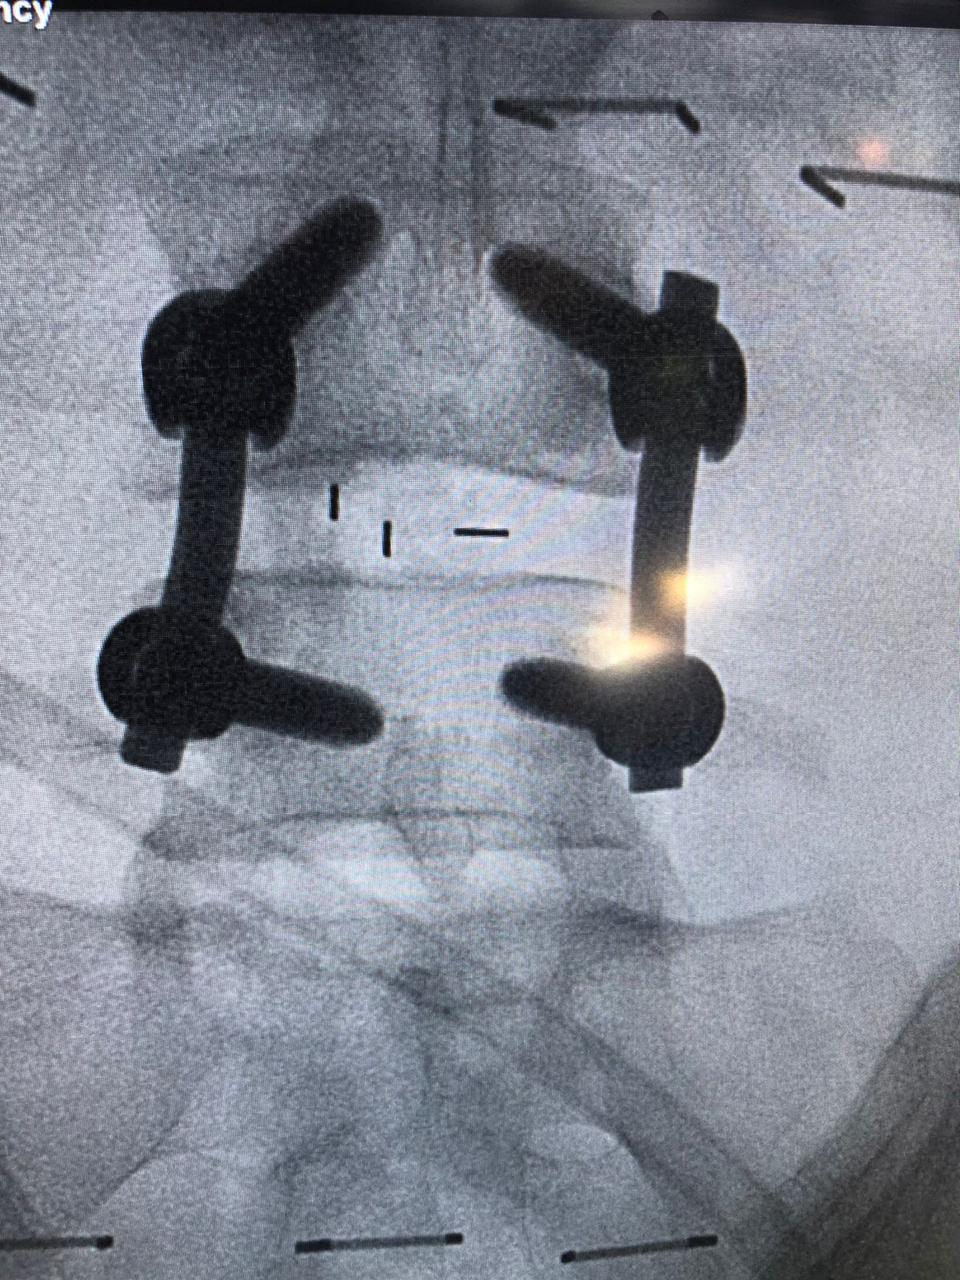

نجح فريق مسار العظام بتجمع الرياض الصحي الأول، من إجراء عملية جراحية معقدة بالعمود الفقري لسيدة خمسينية لا تستطيع الحركة، وذلك بقيادة استشاري جراحة العظام والعمود الفقري د. متعب أبو الراس بمستشفى الملك سلمان بالرياض.

تفاصيل الحالة المرضية

وأوضح د. متعب أبو الراس أن تفاصيل الحالة للمريضة كانت تشكو من آلام مزمنة في الظهر وتمتد إلى الأطراف السفلية مما تؤدي إلى إعاقة قدرتها عن الحركة أو حتى الوقوف، وبعد عمل الفحص الإكلينيكي والأشعة اللازمة تبيّن أن المريضة تعاني من “حالة انزلاق فقاري مصحوب بانزلاق غضروفي وضيق في القناة العصبية بين الفقرتين الرابعة والخامسة القطنية” مع ضرورة التدخل الجراحي.

وأضاف د. أبو الراس بأنه تم إجراء العملية الدقيقة بعد موافقة المريضة عليها وعلى الخطة العلاجية ما بعدها، وتمثلت العملية في توسيع القناة العصبية واستئصال الغضروف ووضع دعامة بين الفقرات مع تصحيح الانزلاق الفقاري وعمل دمج بين الفقرتين الرابعة والخامسة، وتكللت العملية بالنجاح -ولله الحمد- واستطاعت المريضة المشي في أول يوم لها بعد إجراء العملية.